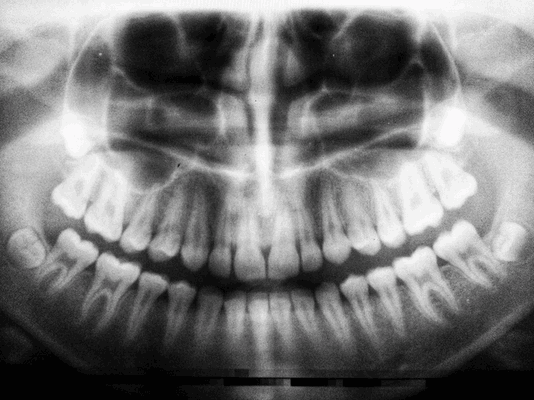

На рентгеновском снимке опорных зубов, участвующих в процессе, в их околоверхушечной области изменения не наблюдаются, однако видна различная степень альвеолярной атрофии. В том случае, если мостовидный протез установлен относительно прочно, трепанировать его опорные зубы или удалять их после снятия моста — грубая ошибка. Обширное вскрытие пародонтального абсцесса ведет к ликвидации процесса и сохранению мостовидного протеза.

Проводится с целью выявить состояние костной ткани и зубных корней, исключить противопоказания. Если вы лечите один зуб, будет достаточно прицельного снимка (рентген). Если врачу необходимо увидеть картину целиком, нужен обзорный снимок (ортопантомограмма). Перед имплантацией вас направят на компьютерную томографию.

Панорамный снимок, КТ. Позволяют увидеть состояние челюстной системы, костной ткани, нервов, носовых пазух. На основании этого врач расписывает план лечения.